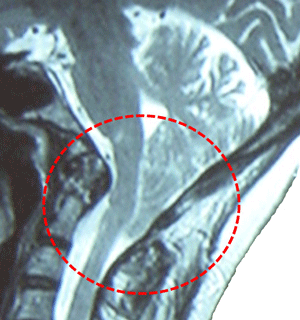

Magnetresonansröntgen (MRI) är den bildprocedur som oftast används för att diagnosticera en Chiari missbildning. Den använder radiovågor och ett kraftfullt magnetfält för att framställa antingen en detaljerad tredimensionell bild eller en tvådimensionell ”skiva” av kroppsstrukturer, sådom vävnader, organ, ben och nerver. Beroende på vilken del/vilka delar av kroppen som skall scannas, kan MRI ta up till en timme att slutföra.

Vänster Chiari missbildning jag med syringomyelia, höger dekomprimering gångjärn kranio-cervikal